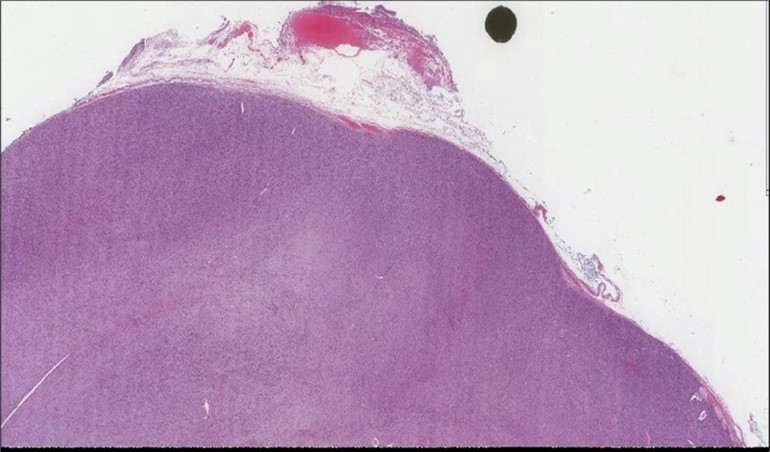

When diagnosing thyroid swelling, imaging studies have been helpful in differentiating malignant from benign tumors with US being used as an initial evaluation tool when assessing thyroid nodules. Tumors are categorized based on composition, echogenicity, shape, margin and echogenic foci into added scores determined by the TI-RADS system, which determines the need for FNA 13. Other imaging modalities include MRI and CT. However; radiological assessment does not distinguish between the types of thyroid cancer, and therefore FNA and biopsy are of crucial importance 3, 6. On a pathologic sample, LMS appears as spindled eosinophilic cells with elongated blunt-ended or cigar-like nuclei arranged in fascicles 2, 7 (Figure 1, Figure 2, Figure 3). Despite the unique microscopic morphology, LMS cannot be distinguished from other spindle cell tumors such as spindle cell variant of medullary thyroid cancer, anaplastic thyroid

Figure 1.Left thyroid Low power of the thyroid gland showing complete replacement of the thyroid by the neoplastic cells (H&E, ×4).